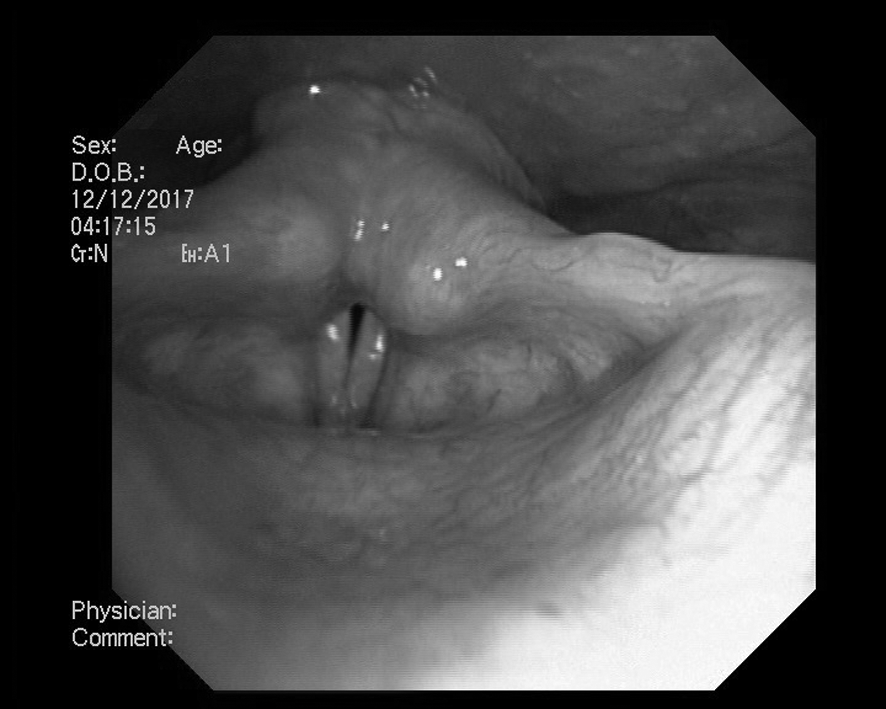

Положение голосовых складок во время фонации представлено на рис. 2. Голосовая щель симметрична. При фонации отмечается неполное смыкание в задней трети (расхождение составляет до 0,2 см) за счет левой голосовой складки. Диагноз: парез гортани слева.

Рис. 2. Парез гортани слева. Положение голосовых складок при фонации. Латеральное положение левой голосовой складки. До начала лечения.